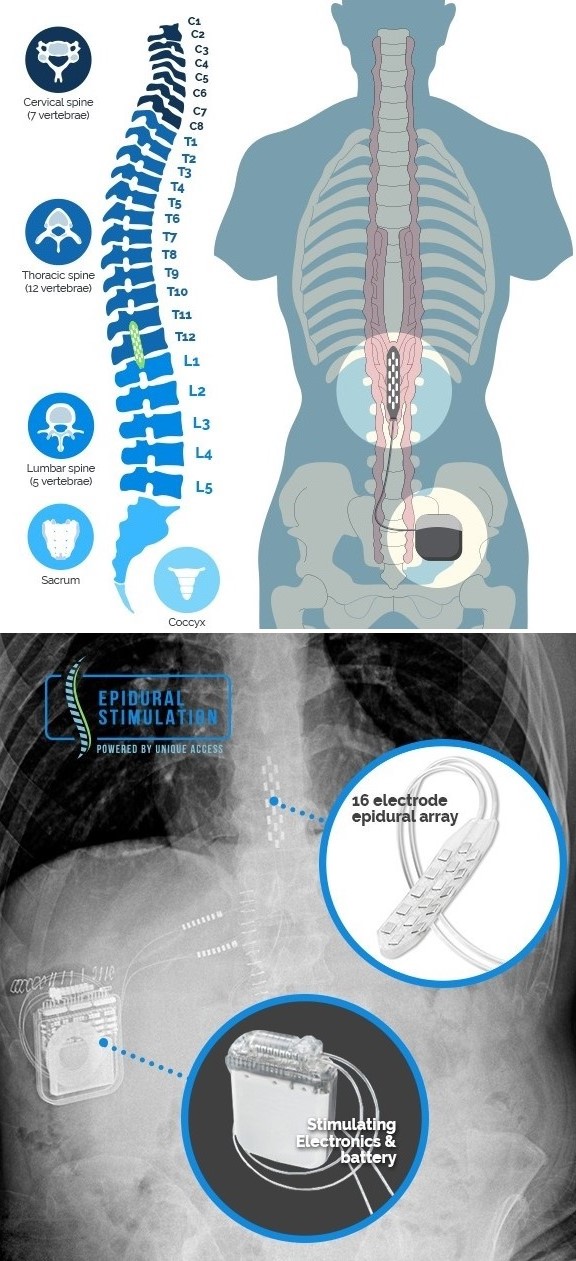

درد نروپاتیک یکی از انواع پیچیده و مقاوم به درمان درد است که ناشی از آسیب به سیستم عصبی میباشد. این درد معمولاً به صورت سوزش، تیرکشیدن، یا گزگز در ناحیه آسیب دیده احساس میشود و میتواند زندگی روزمره افراد را به شدت تحت تأثیر قرار دهد. از آنجایی که این نوع درد به درمانهای معمولی پاسخ نمیدهد، روشهای پیشرفتهتری مورد استفاده قرار میگیرند. یکی از این روشها، پروتز عصبی تحریک نخاعی اپیدورال است که در آن الکترود سطحی بهطور دائمی یا موقت در ناحیه قفسه سینهای نخاع قرار داده میشود تا با ارسال سیگنالهای الکتریکی با پارامترهای و الگوهای متنوع، انتقال درد به مغز را از طریق تئوری دروازه (Gate Theory) مهار کند. این روش میتواند به طور مؤثری درد را کاهش داده و کیفیت زندگی بیماران را بهبود بخشد.